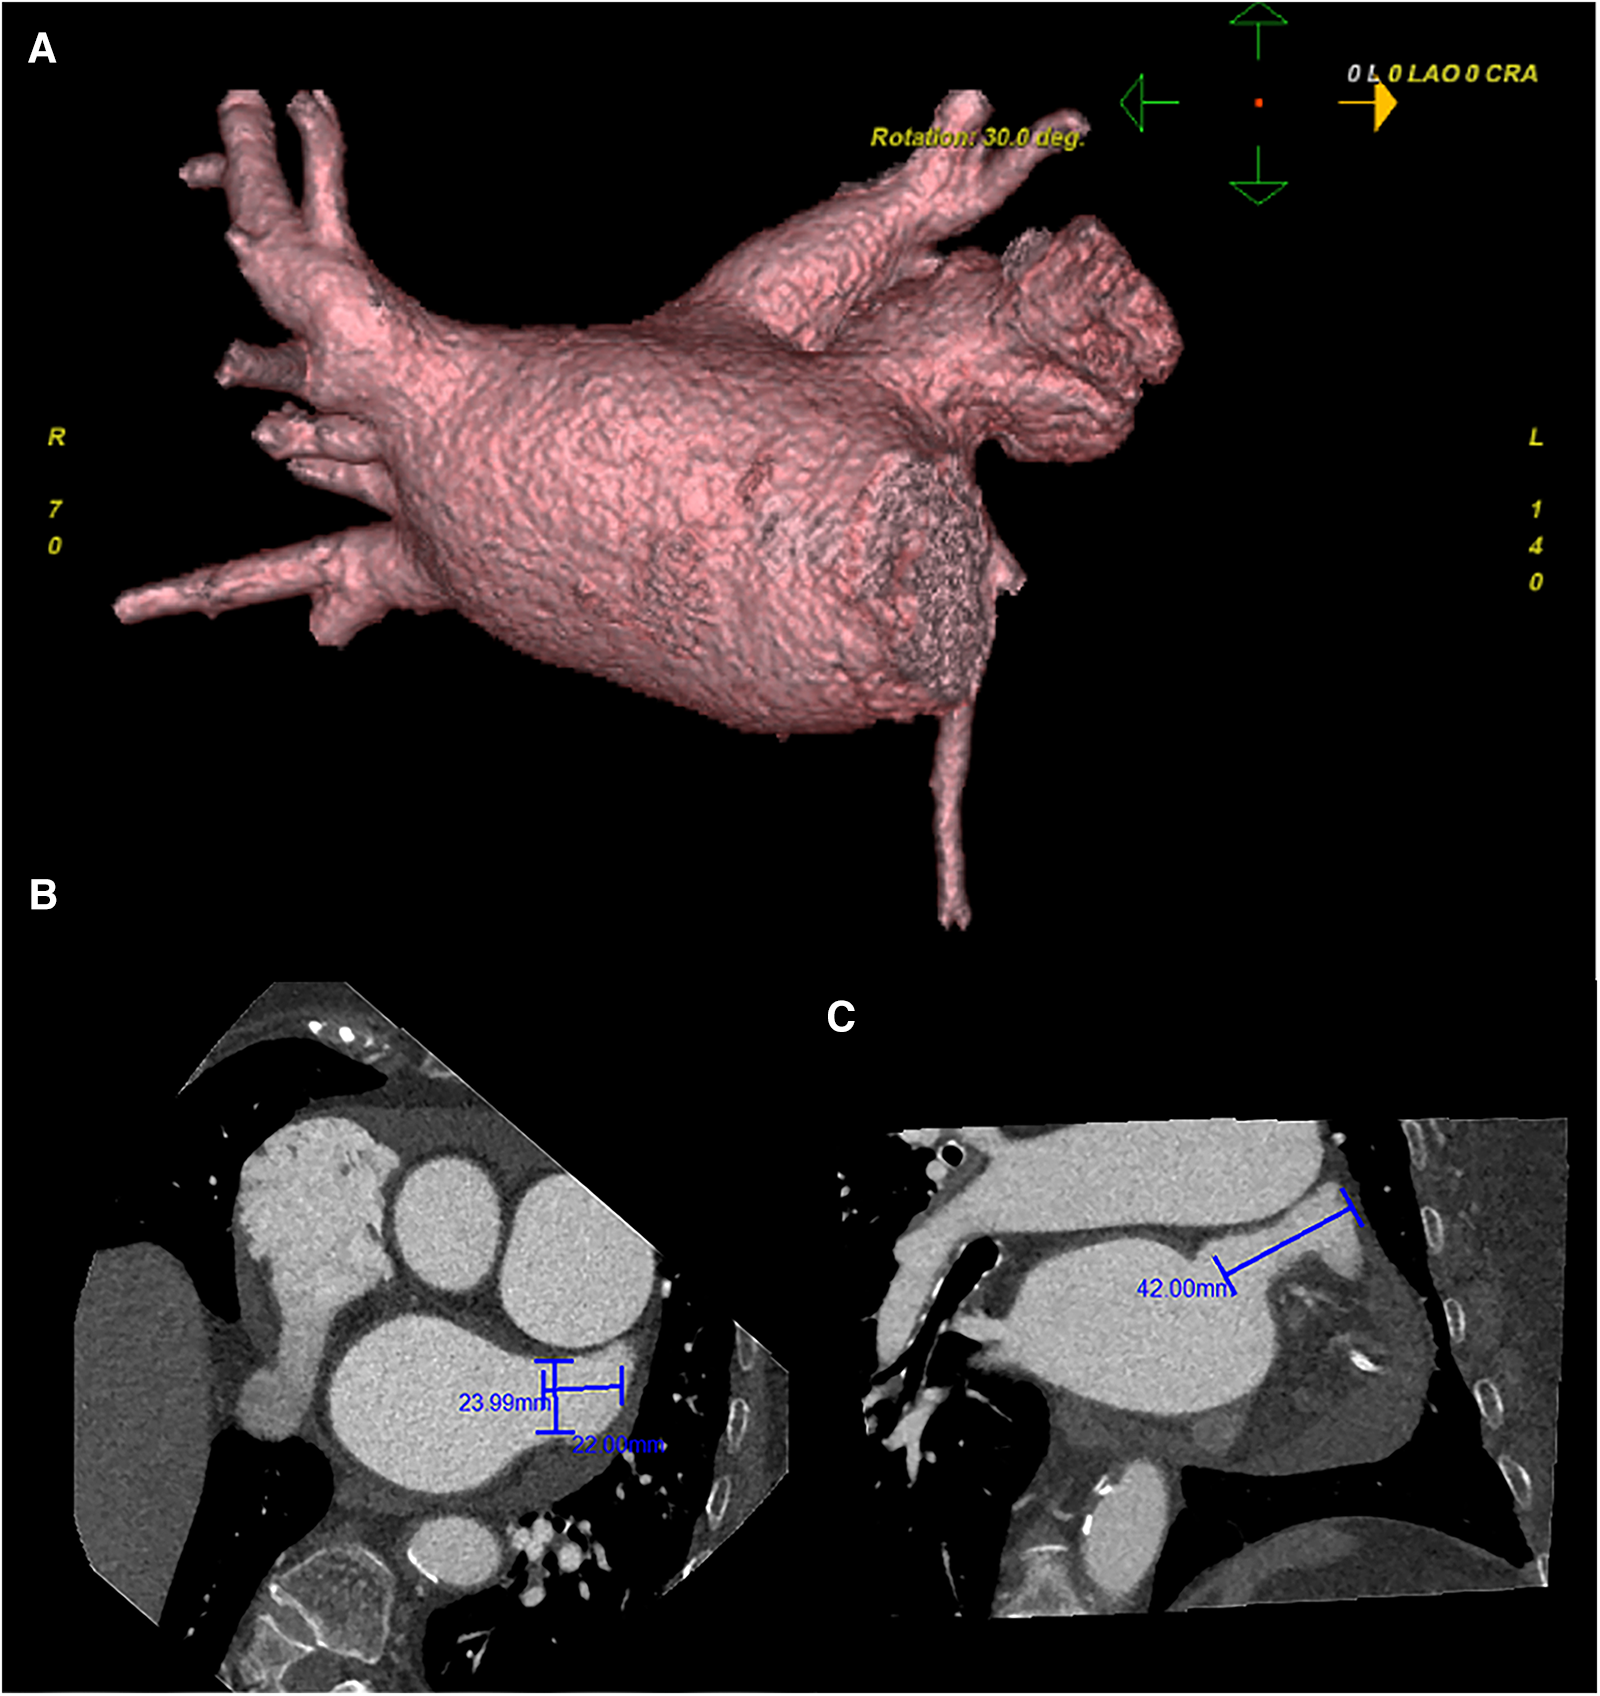

Preoperative left atrial CT angiography showed that the left atrial appendage was complex with a large branch, while no evident filling defect was observed in both the left atrial appendage and left atrium. No diverticulum or accessory atrial appendage was observed in the left atrium (Figure 1). Laboratory tests on the morning of surgery revealed a hemoglobin count of 117 g/L, a platelet count of 115 × 109/L, and an international normalized ratio (INR) of 0.96.

Figure 1

Preoperative cardiac CT angiography reveals a complex left atrial appendage with a large branch, no clear filling defect in the left atrial appendage and left atrium, and no diverticulum and accessory atrial appendage was identified in the left atrium (A) the cross-sectional image of the LAA orifice (B) the long diameter was about 2.4 cm, the short was about 2.2 cm. Oblique view (C) the maximum depth of the left atrial appendage branch was about 4.2 cm. Pericardial effusion.